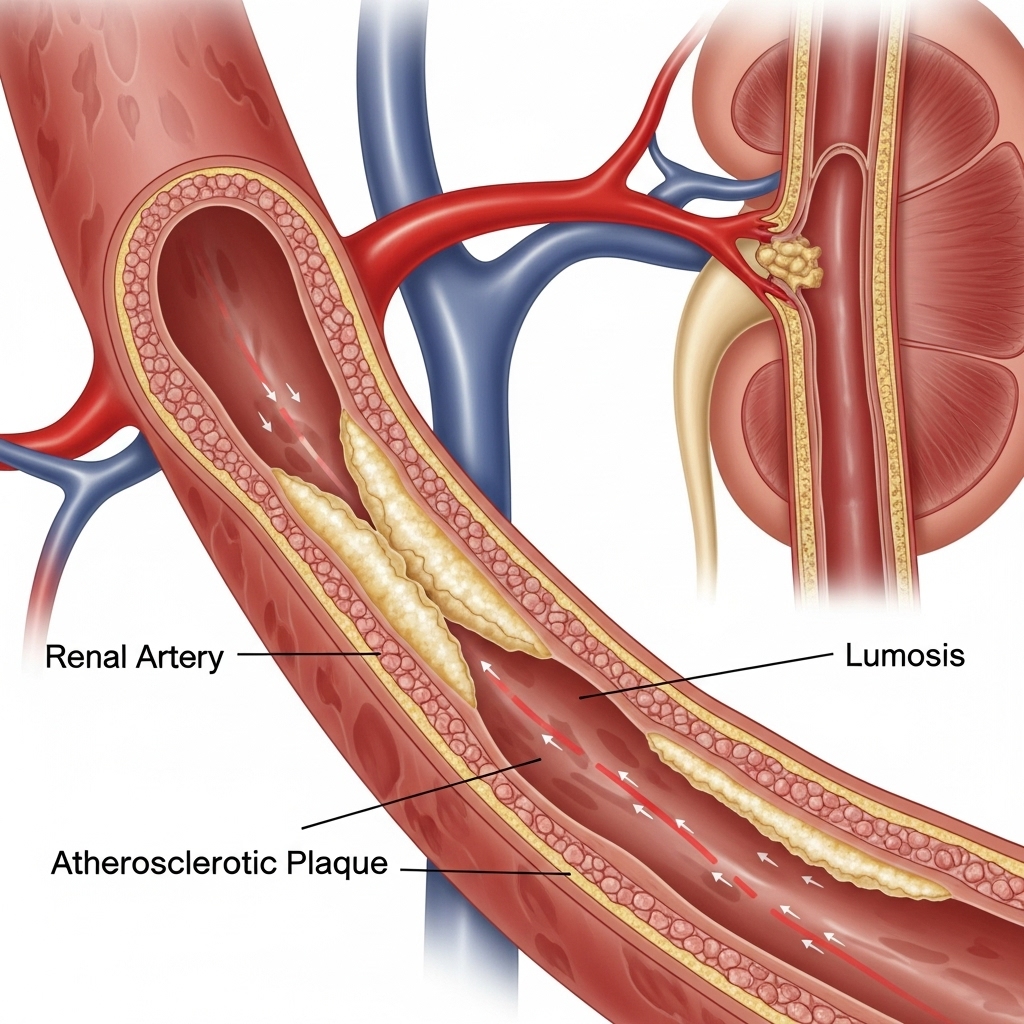

Renal artery stenosis (RAS) is a condition where the arteries that supply blood to your kidneys become narrowed or blocked. This kidney artery narrowing reduces blood flow to the kidneys, leading to high blood pressure and potentially serious complications if left untreated. Understanding this condition is the first step toward effective management and recovery.

Our state-of-the-art facilities utilize advanced imaging technology for accurate diagnosis:

Detailed imaging that provides clear pictures of the renal arteries and any narrowing.

The gold standard for diagnosing renal artery stenosis with precise visualization.